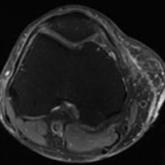

ArticleLower Limb Morel-Lavallée Lesion Treated With Short-Stretch Compression BandagingAuthor:Robin W. Kauffman, PT, CLT-LANAPublish date: July 20, 2017Morel-Lavallée lesions (MLLs) classically occur in the greater trochanteric region, lateral thigh, buttocks, and back. A high percentage of large M...Read More